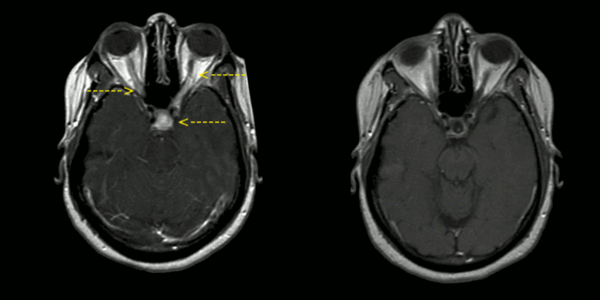

Магнитно-резонансная томография считается наиболее чувствительным методом диагностики НС, хотя изменения также неспецифичны. В 30—40 % случаев выявляется поражение оболочек основания головного мозга, очаговые изменения белого вещества и вовлечение гипоталамо-гипофизарной области. В 14 % случаев наблюдаются псевдотуморозные изменения, реже — гидроцефалия. В активной фазе заболевания характерно накопление гадолиния в поражённых участках[5].